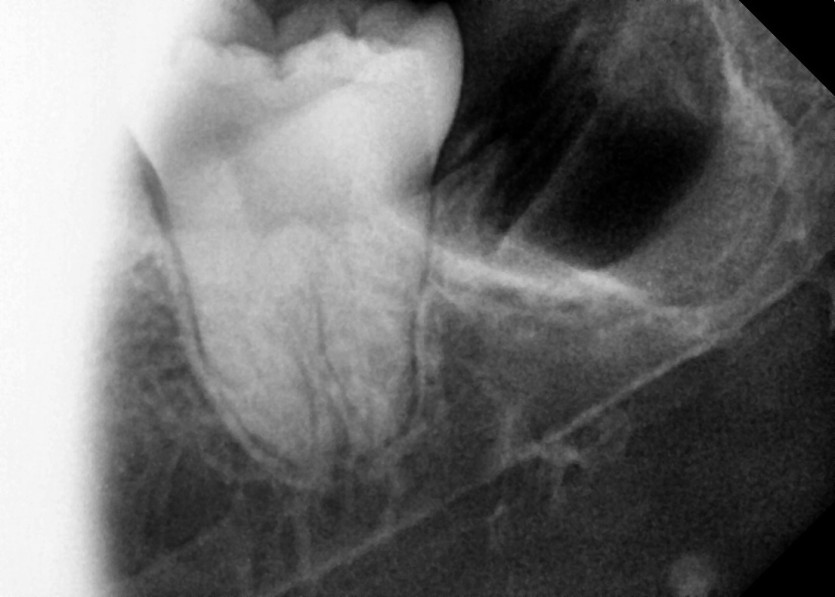

#38,48 사랑니 발치

구강 외과 전문의가 당일 발치했습니다.